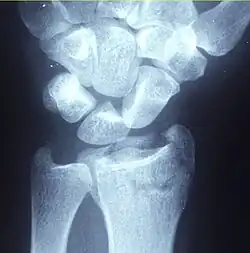

| Other names: Broken wrist[1] | |

![]() | |

| A Colles fracture as seen on X-ray: It is a type of distal radius fracture. | |